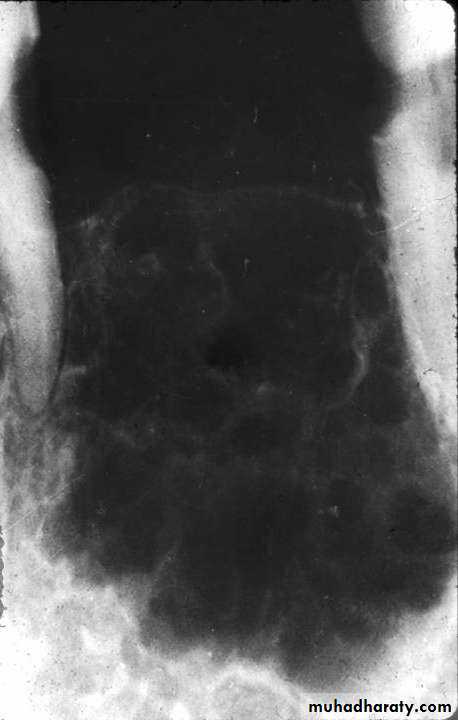

• Radiography:• Typically appears as multi locular radiolucent area with well defined scalloped margin or soap bubble.

• Copyright 2003, Elsevier Science (USA). All rights reserved.

• Odontogenic myxoma

• Treatment :• Small odontogenic myxomas are treated by curettage, while larger lesions may require surgical resection.

• Odontogenic myxomas are not encapsulated and tend to infiltrate adjacent tissues.

• Recurrence rates of up to 25 % are reported.

• Overall, the prognosis is good for most odontogenic myxomas.